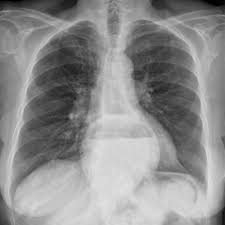

Aufgeblähter Bauch durch Bewegungsmangel Ein Mangel an Bewegung kann schnell zu einem Gasbauch führen. Aufgeblähter Oberbauch mit Atemnot Bei einer ausgeprägten Schwellung des Oberbauchs kann es zu einer Beeinträchtigung der Atmung kommen da der Bauch von unten auf die Lungenflügel drückt und deren Entfaltung beeinträchtigt. Gegen die Beschwerden lässt sich einiges tun.

Aufgeblähter Oberbauch mit Atemnot Bei einer ausgeprägten Schwellung des Oberbauchs kann es zu einer Beeinträchtigung der Atmung kommen da der Bauch von unten auf die Lungenflügel drückt und deren Entfaltung beeinträchtigt. Sie empfinden sich als unangenehm aufgebläht und haben oft zusätzlich Bauchkrämpfe. Symptome einer akuten Pankreatitis knnen sein es mssen nicht alle Symptome auftreten akut auftretender heftiger Schmerz im Oberbauch Epigastrium der oft grtelfrmig in den Rcken ausstrahlt. Gegen die Beschwerden lässt sich einiges tun. 07032016 Klumpiger harter Stuhlgang oder ber einen lngeren Zeitraum berhaupt kein Stuhlgang sind die typischen Anzeichen einer Verstopfung. Belkeit Erbrechen Fieber ein aufgeblhter Bauch sowie starke Bauchschmerzen. Kurzatmigkeit und mühsames Atmen Atemnot. Zungenpilz Ursachen Und Behandlung Heilpraxis. Der Zustand verschwindet kommt später aber wieder - dann auch mit starker Atemnot.